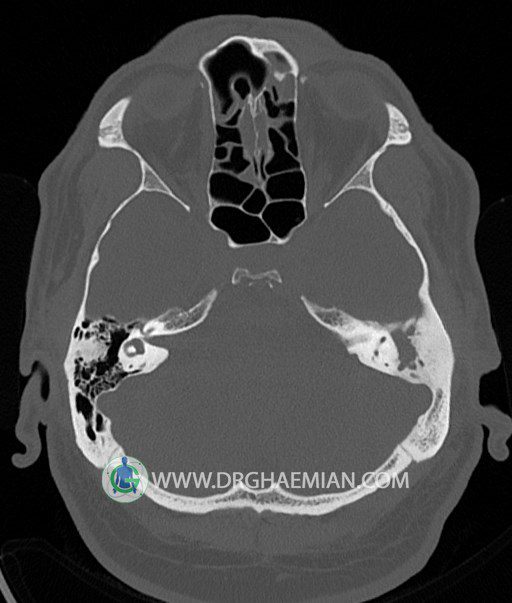

سی تی اسکن گوش داخلی به رادیولوژیست اجازه می دهد تا سطوح مختلف، یا اسلایس هایی از استخوان های که از جمجه به گوش می روند را از طریق امواج ایکس چرخشی مشاهده کند. در این کیس اودیت مدیا، ماستوئیدیت مزمن، اوتیت خارجی، انحراف سپتوم بینی، کونکا بولوزا و افزایش ضخامت سینوس ها مشاهده می شود.

در HRCT از استخوان تمپورال با مقاطع آگزيال ، ساژيتال و کرونال ظريف ( 0.6 mm ) :

– نماي کوکلهآي دو طرف با 2.5 دور گردش مجرا

– نماي cochlear aqueduct

– نماي semicircular canal خلفي ، لترال ، فوقاني و وستيبول

– استخوانچه هاي گوش داخلي شامل malleus ، incus و stapes (دنسيتي و رديف استخوانچه ها )

– نماي oval window و round window ، tympanic cavity ، attic و کانال گوش داخلي

– کانال عصب فاشيال و مسير ان از ناحيه کانال گوش داخلي ، geniculate ganglion تا محل خروج ان از stylomastoid foramen

– نماي tympanic membrane ، کانال ICA ، بولب جوگولار دو طرف

در حد طبيعي است .

– اپاسيتي گوش مياني چپ ناشي از وجود دانسيته نسج نرمي دراطراف استخوانچه ها همراه با اروژن اسکوتوم و

استخوانچه ها بدون جابجايي در رديف استخوانچه ها مشهود است که مطرح کننده اوتيت مديا همراه با نشانه

هاي مشکوک به کولستئاتوم مي باشد .

– اپاسيتي و اسکلروزيس ماستوئيد چپ نشانه ماستوئيديت مزمن

– اپاسيتي کانال گوش خارجي ناشي از دانسيتي نسج نرمي مطرح کننده external otitis

– انحراف سپتوم مياني بيني به راست

– کونکا بولوزا در کونکاي مياني چپ و

– افزايش ضخامت مخاطي در سينوس هاي اتموئيد و ماگزيلاري

اپاسيته